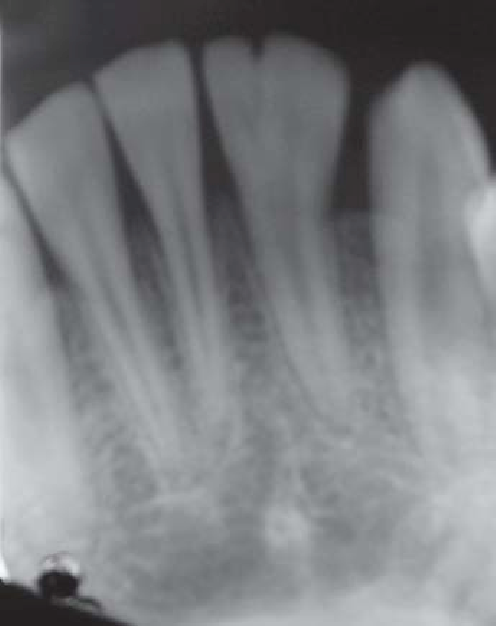

9 / 25

9. (Select ONE or MORE correct answer)

The radiograph shows evidence of